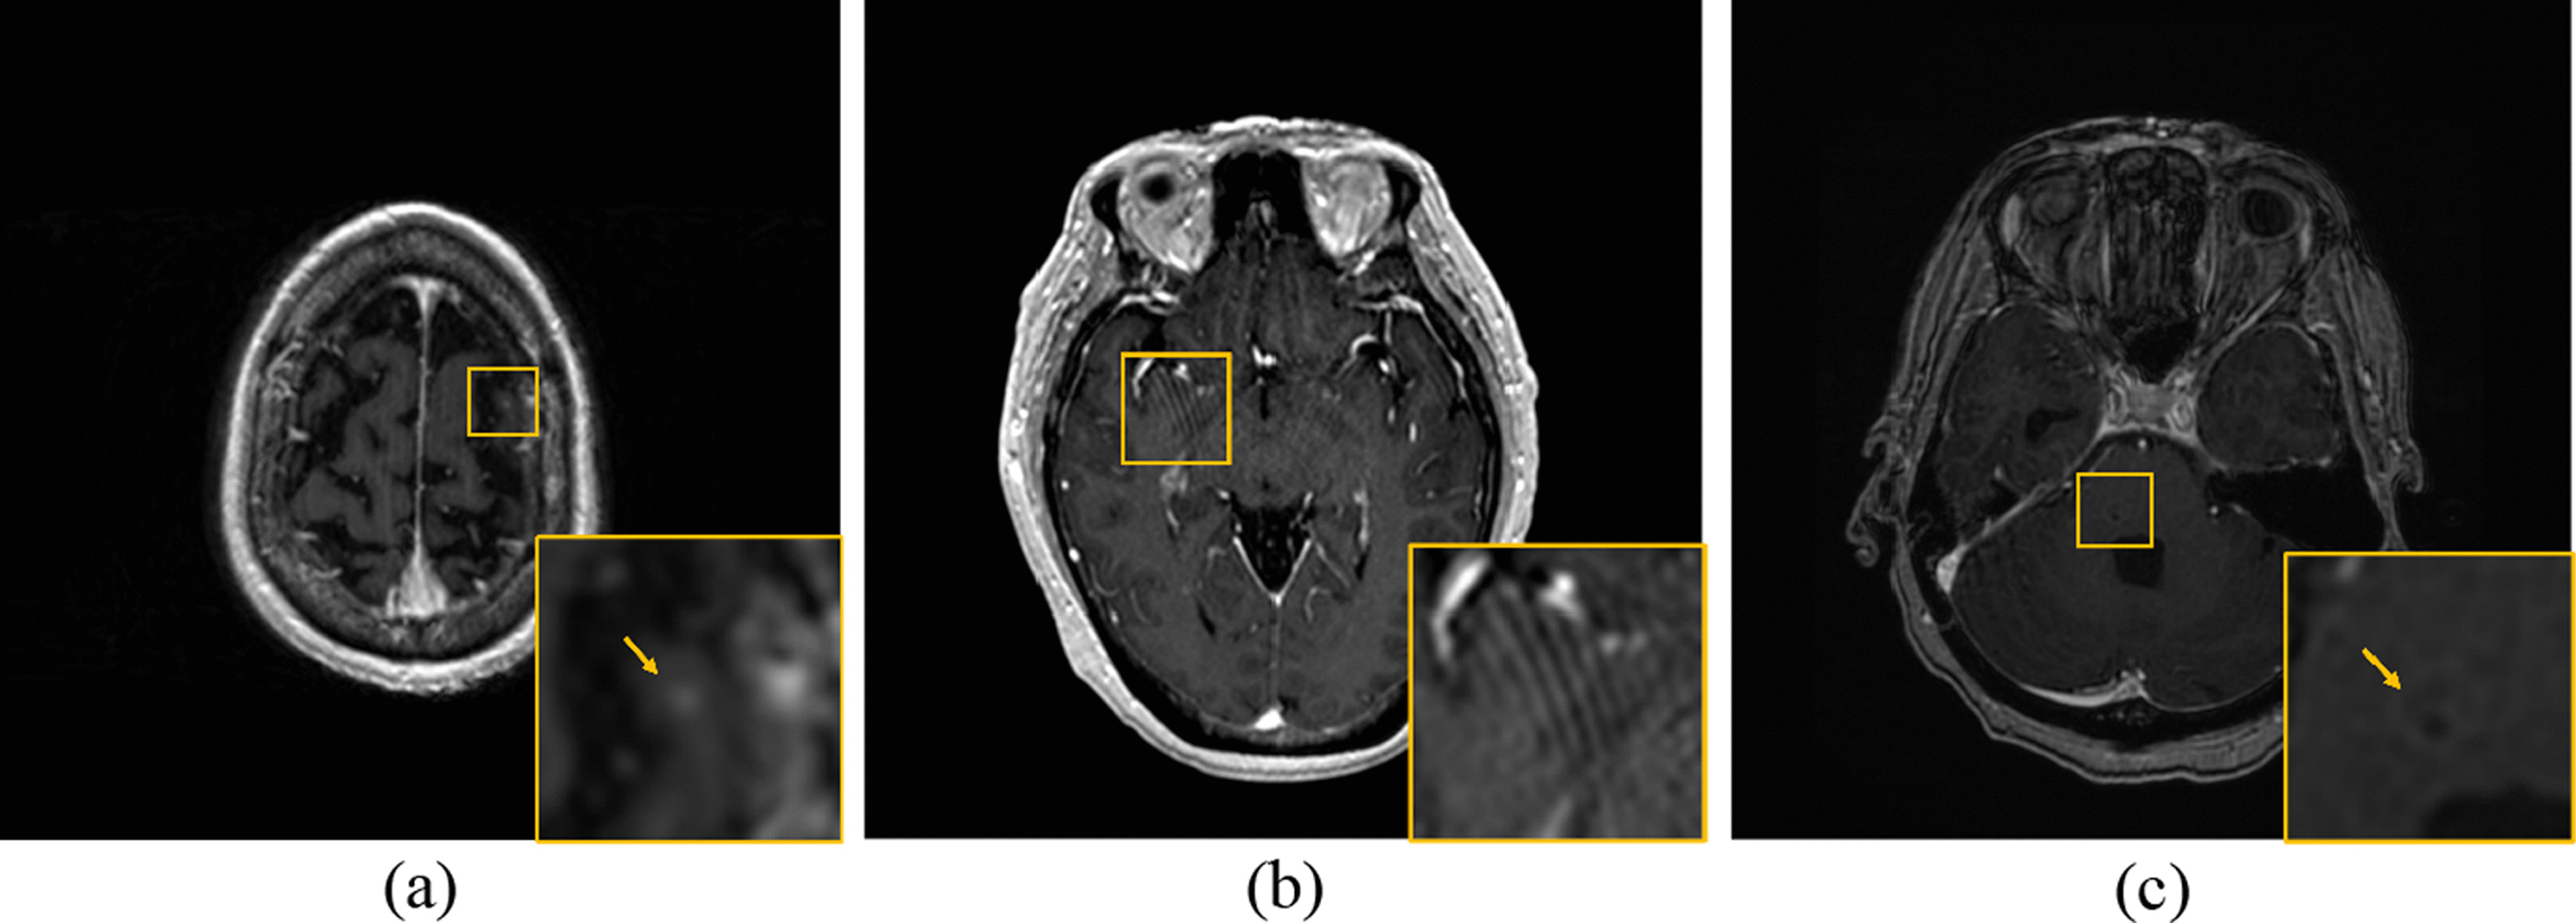

Figure 1 and Fig. 2 illustrate cases in which VBrain effectively predicted brain metastases among patients with numerous lesions (52) and lesions of small size (2.5 and 4.2 mm diameters). Figure 3 demonstrates challenging cases with tiny lesions, poor image quality, or insufficient contrast in the MR scan for which diagnostic reports and/or longitudinal images might be required for additional reference. No other statistically significant differences in performance metrics were observed across demographic and clinical characteristic groups.

Fig. 3.

Challenging Cases: a Tiny Lesion. (0.02 c.c.) b Image Artifacts. c Insufficient Contrast. In these cases, the diagnostic report and longitudinal images may be required for additional reference